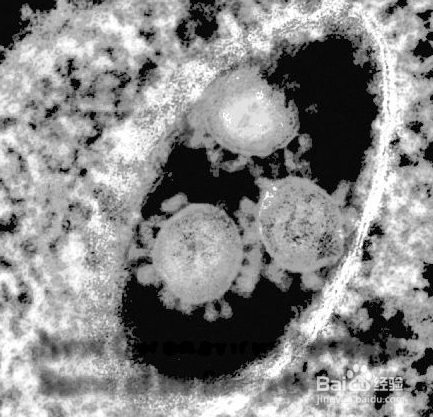

新型冠状病毒肺炎的早期症状是什么

1、通常会有发热,乏力,干咳

2、有些患者不会出现发热咳嗽的情况

3、有可能出现乏力精神差

4、恶心呕吐,腹泻等

5、有的以神经系统症状:如头疼

6、有的以心慌胸闷等